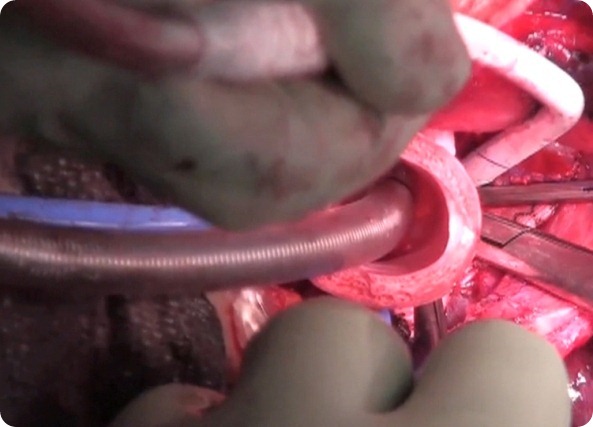

Meanwhile, researchers at Harvard Bioscience Inc. of Holliston, Mass., made a bioreactor. The artificial scaffold was placed on the bioreactor, and stem cells extracted from the patient's bone marrow were dripped onto the revolving scaffold for two days. Dr. Macchiarini and colleagues then added chemicals to the stem cells, persuading them to differentiate into tissue—such as bony cells—that make up the windpipe.